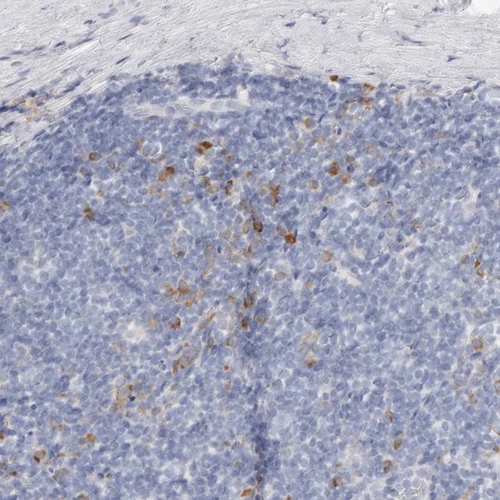

Immunohistochemical staining of human tonsil shows strong cytoplasmic positivity in germinal center cells.